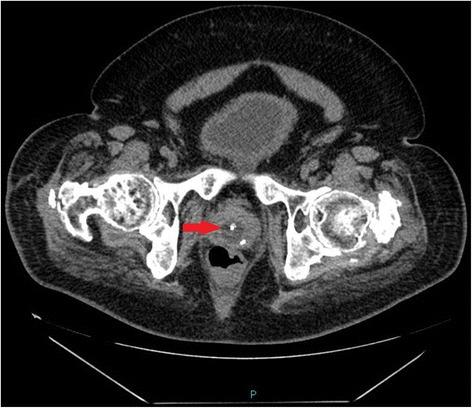

A tetraplegic patient started sweating profusely following insertion of a Foley catheter per urethra. The catheter was draining urine; there was no bypassing, no bleeding per urethra, and no haematuria. Patient's wife, who had been looking after her tetraplegic husband for more than forty years, told the health professionals that the catheter might have been placed incorrectly but her concerns were ignored. Ultrasound scan of urinary tract revealed no urinary calculi, no hydronephrosis. The balloon of Foley catheter was not seen in urinary bladder but this finding was not recognised by radiologist and spinal cord physician. Patient continued to sweat profusely; therefore, CT of pelvis was performed, but there was a delay of ten days. CT revealed the balloon of Foley catheter in the over-stretched prostate-membranous urethra; the tip of catheter was not located within the urinary bladder but was lying distal to bladder neck. Flexible cystoscopy was performed and Foley catheter was inserted into the bladder over a guide wire. The intensity of sweating decreased; noxious stimuli arising from traumatised urethra might take a long while to settle.